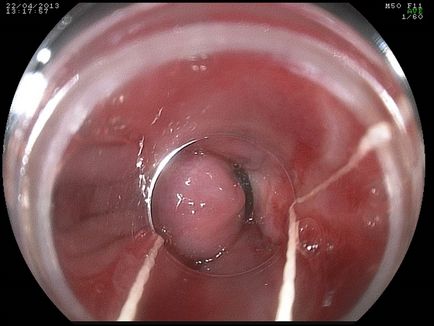

Наочний приклад кільця стравоходу на записи ендоскопічного дослідження.

Ендоскопічне обстеження зазвичай використовується для того, щоб отримати візуальну картину патологічних змін в стравоході. За допомогою ендоскопа, який вводиться в стравохід через ротову порожнину, можна вивести зображення на екрани моніторів. Сучасна оптична апаратура дозволяє отримувати якісну картинку.

До недоліку ендоскопії можна віднести те, що трубці може бути складно просуватися до нижнього сегменту органу через значне звуження просвіту. При наявності результатів мінімум таких двох діагностик досвідчені лікарі можуть поставити діагноз з більшою точністю.